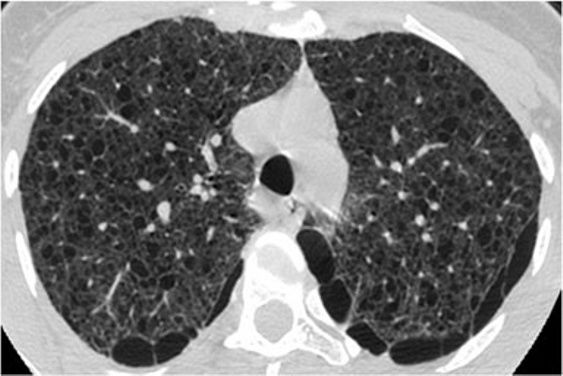

8、囊性病变

囊性模式由界限分明,圆形和外接空气的实质组成,有界限分明的壁和与正常肺。

经典疾病:淋巴管平滑肌肌瘤病(LAM),其特征是通常存在圆形的薄壁肺囊肿,没有在局部明显的特点,分布广泛,包括肋骨角和肺底。 LAM可能伴有胸水表现为胸膜胸腔积液。鉴别诊断是随机分布的囊肿,临床病史表现几乎只影响着育龄妇女。鉴别疾病:是肺组织细胞增生症、淋巴细胞性间质性肺炎(LIP)和小叶性肺气肿。

*LAM。上叶水平的HRCT表现出“囊性模式”,其特征是位于肺实质和隔中的许多大小不等的薄壁“真”囊腔的存在。

肺组织细胞增生症在处于纯囊性期(纯结节性和结节性-囊性期之后的第三期)时模拟LAM。它的特征是存在薄壁和厚壁的囊、形状呈异形,类似于苜蓿叶。囊肿具有特征性以上部和中部肺区分布为主。

*组织细胞增多症。上叶水平的HRCT揭示了一种“囊肿型”,其特征是许多薄或厚的“真”囊肿,形状奇异,大小不一。在右胸膜腔中发现引流导管以治疗气胸,这是这位27岁重度吸烟患者。